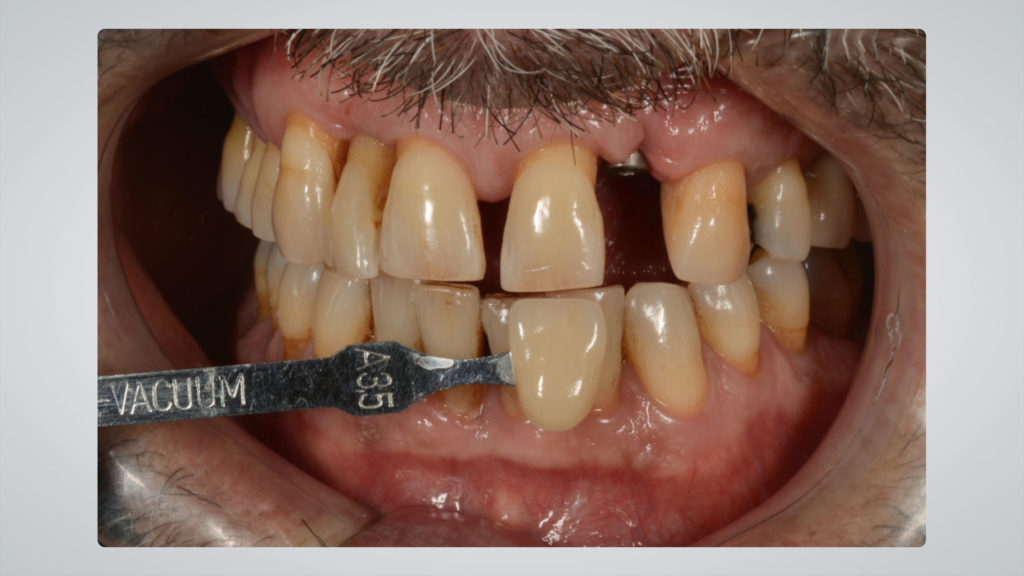

Die Implantatkrone sollte metallkeramisch gelöst werden, was wiederum bedeutete, dass für die entsprechend designte Implantatkrone ein CAD/CAM-gestützt gefertigtes Abutment (vorgefertigt, Schweden & Martina) mit einer Metallkeramik (Ceramco 3, Dentsply Sirona) verblendet werden musste. Es wurde eine zementierte Lösung gewählt, weshalb es keinen Schraubenkanal gab und somit keine Probleme mit dessen Austritt gelöst werden mussten. In den Abbildungen 6a und 6b sind die DSLR-Aufnahmen des Behandlers dargestellt. Die Referenzfarbmuster vermitteln die ungefähre Zahnfarbe, aber nicht alle Informationen und Merkmale, die für die Rekonstruktion des natürlichen Zahns vonnöten sind. Indem man die Belichtung reduziert und den Kontrast sowie die Brillanz in einem Bildbearbeitungsprogramm wie Lightroom (Adobe) erhöht, lässt sich die Histoanatomie des natürlichen Zahns besser darstellen (Abb. 6c).

Nachdem die Farbanalyse abgeschlossen war, wählten wir die für die keramische Verblendung erforderlichen Massen gemäß der Referenztabelle des Ceramco 3-Systems aus. So wurde gewährleistet, dass wir das, was wir analysiert haben und nachahmen wollten, auch mit den entsprechenden Massen nachahmen konnten (Abb. 10). Den Anfang machte das Opakern des Metallgerüsts. Dafür kam der Ceramco 3-Pastenopaker zum Einsatz, auf den noch zusätzlich der systemimmanente Pulveropaker gestreut wurde. Dies sorgte für eine rauere Oberfläche, an der sich das Licht diffus brechen konnte. Nach dem Brand stellte sich das Ergebnis wie in Abbildung 11 zu sehen dar. Der Behandler hatte als Grundzahnfarbe die A3,5 und für den freiliegenden Wurzelbereich B4 ausgewählt. Dementsprechend wurden die Massen gewählt (Abb. 12 und 13). Darüber hinaus verwendeten wir, wie aus den Fotografien, die mit Kreuzpolfilter angefertigt worden waren, ersichtlich (vgl. Abb. 8a und b), im inzisalen Drittel eine Dentin-Masse mit geringerem Helligkeitswert (Abb. 14 und 15).